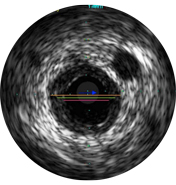

Внутрисосудистое ультразвуковое исследование (ВСУЗИ) — это технология, которая позволяет визуализировать кровеносные сосуды изнутри с использованием катетера. Данные изображения помогают оценить наличие и степень заболевания, форму и морфологию бляшки, контролировать положение проводника во время прохождения поражения и позиционирование стента после процедуры. Датчик, формирующий изображение, излучает высокочастотные звуковые импульсы, которые отражаются от стенок сосуда и улавливаются сенсорами, при этом интенсивность сигнала колеблется в зависимости от характеристик ткани. Система обрабатывает электронный сигнал и преобразует его в изображение.

Диаметры сосудов можно определять в проксимальных и дистальных контрольных точках за счет значений диаметров просветов, средних диаметров стенок (в центральной точке между просветом и сосудом) или диаметров сосудов.

ВСУЗИ помогает более точно определить степень и тип стеноза (т.е. минимальную площадь просвета (MLA), объем бляшки и кальций). Несмотря на то что ВСУЗИ позволяет выявить разрыв бляшки, наличие тромбов и диссекции, кальций наиболее распространен при рутинных ЧКВ. Оказывая большее влияние на стратегию стентирования, кальций отображается в виде очень ярких участков с акустическим затенением, которое блокирует изображение сзади. Также могут наблюдаться реверберации.